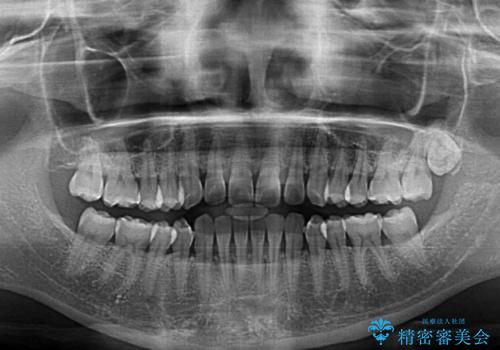

前歯の隙間と上下正中のズレを解消

- 上下前歯隙間と正中のズレを改善したいとのことで来院された患者様です。

正中がなかなか合わずに、2年近くの治療期間を要しました。